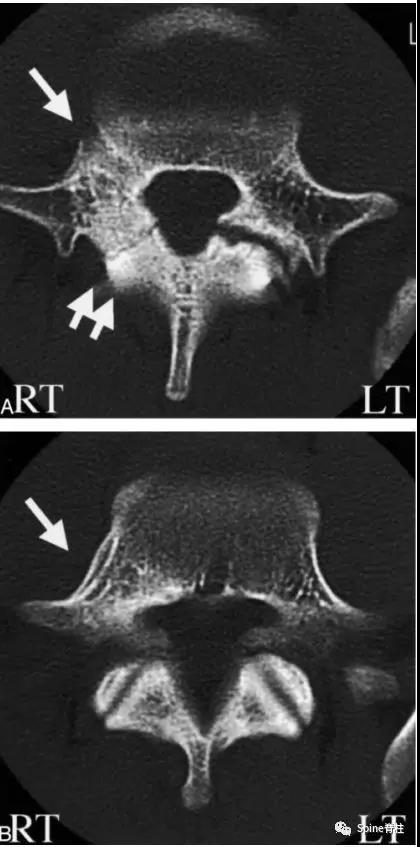

2003年发表在Am J Sports Med杂志(IF=6.20)上的病例报道,很好的阐述了峡部裂和椎弓根裂的变化。描述一个17岁的棒球运动员,运动后腰痛1月余,随访的辅助检查提示相同椎体水平出现的3个连续性应力性骨折:第一次为左侧峡部,第二次为右侧椎弓根,第三次为右侧峡部。

图:起始CT提示L5左侧峡部裂(双箭头),起始CT检查后2个月复查可见出现右侧椎弓根裂(单箭头),4个月复查可见椎弓根裂愈合(单箭头)